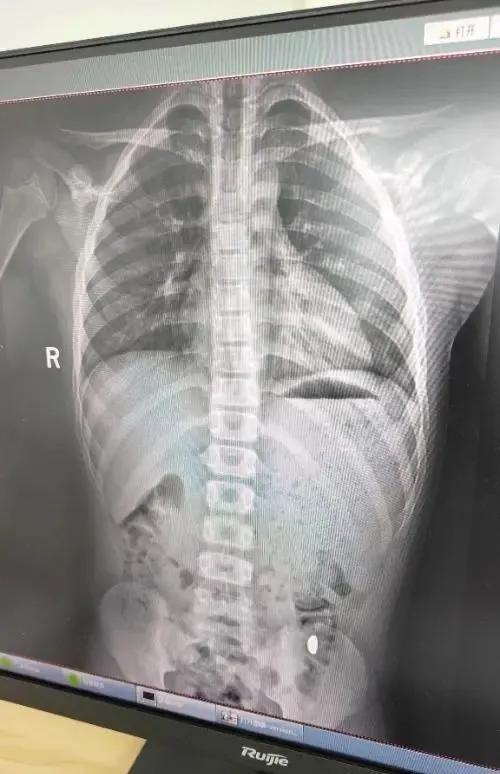

10月26日上午9時,紀女士帶兒子前往昆山市第五人民醫院就診。門診醫生詳細詢問了誤吞時間、物品性質和后續癥狀。體格檢查顯示孩子生命體征平穩,腹部無壓痛。醫生建議進行影像學檢查,X光片清晰顯示胃部存在高密度陰影,確診為金屬異物滯留。

醫生給出兩種處理方案:立即通過胃鏡取出或繼續觀察等待自然排出??紤]到孩子沒有不適癥狀且異物邊緣圓滑,醫患雙方選擇保守治療。醫生開具促進胃腸蠕動的藥物,囑咐如出現腹痛、便血等異常立即復診。紀女士支付了總計386元的檢查費和藥費。